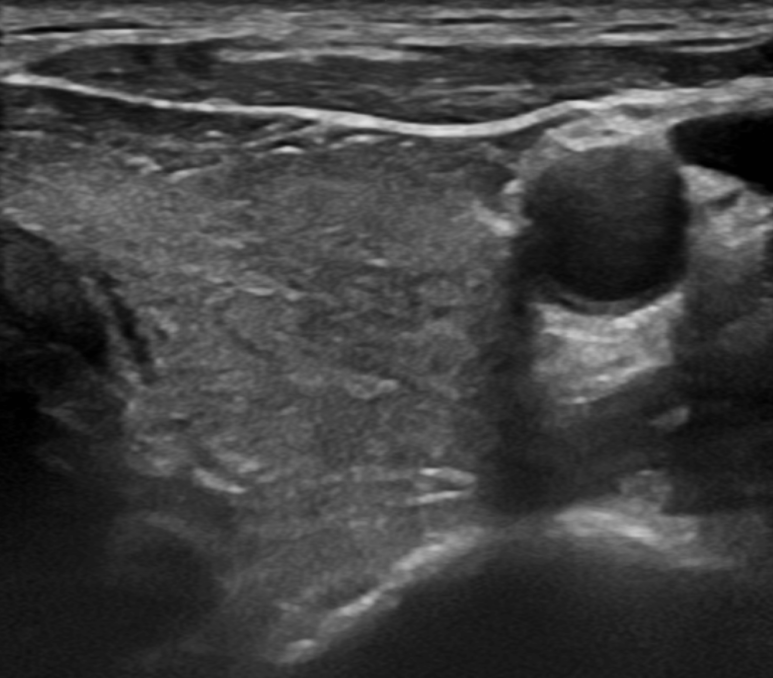

갑상선 초음파이기 때문에 갑상선 초음파를 봅니다만, 검사 전문의 진상 관련 증상이 명확하지 않았기 때문에 예상 밖의 소견이었습니다.

갑상선 표면이 고르지 못하고(Heterogenouse chogenicity) 혈관이 매우 발달되어 있습니다(hypervascularity).

초음파 소견만으로 갑상선 저하 항진인지는 정확한 구분은 어렵지만 갑상선 호르몬의 수치에 이상이 있는 것은 확실합니다.